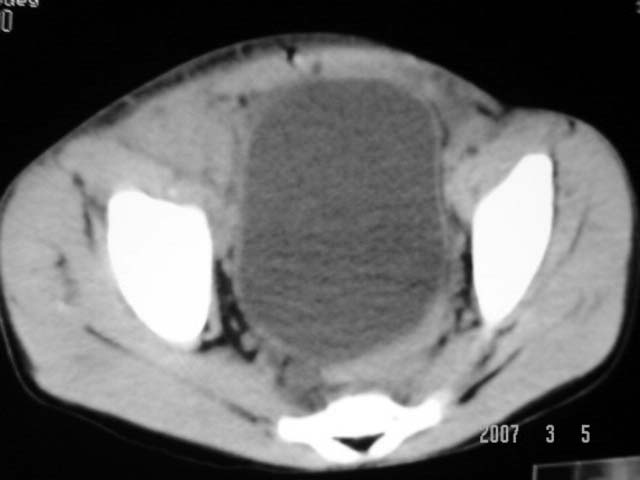

以下是引用dyqct在2007-3-5 10:28:00的发言:[br]右髂窝肿块。[br][br][br][br]